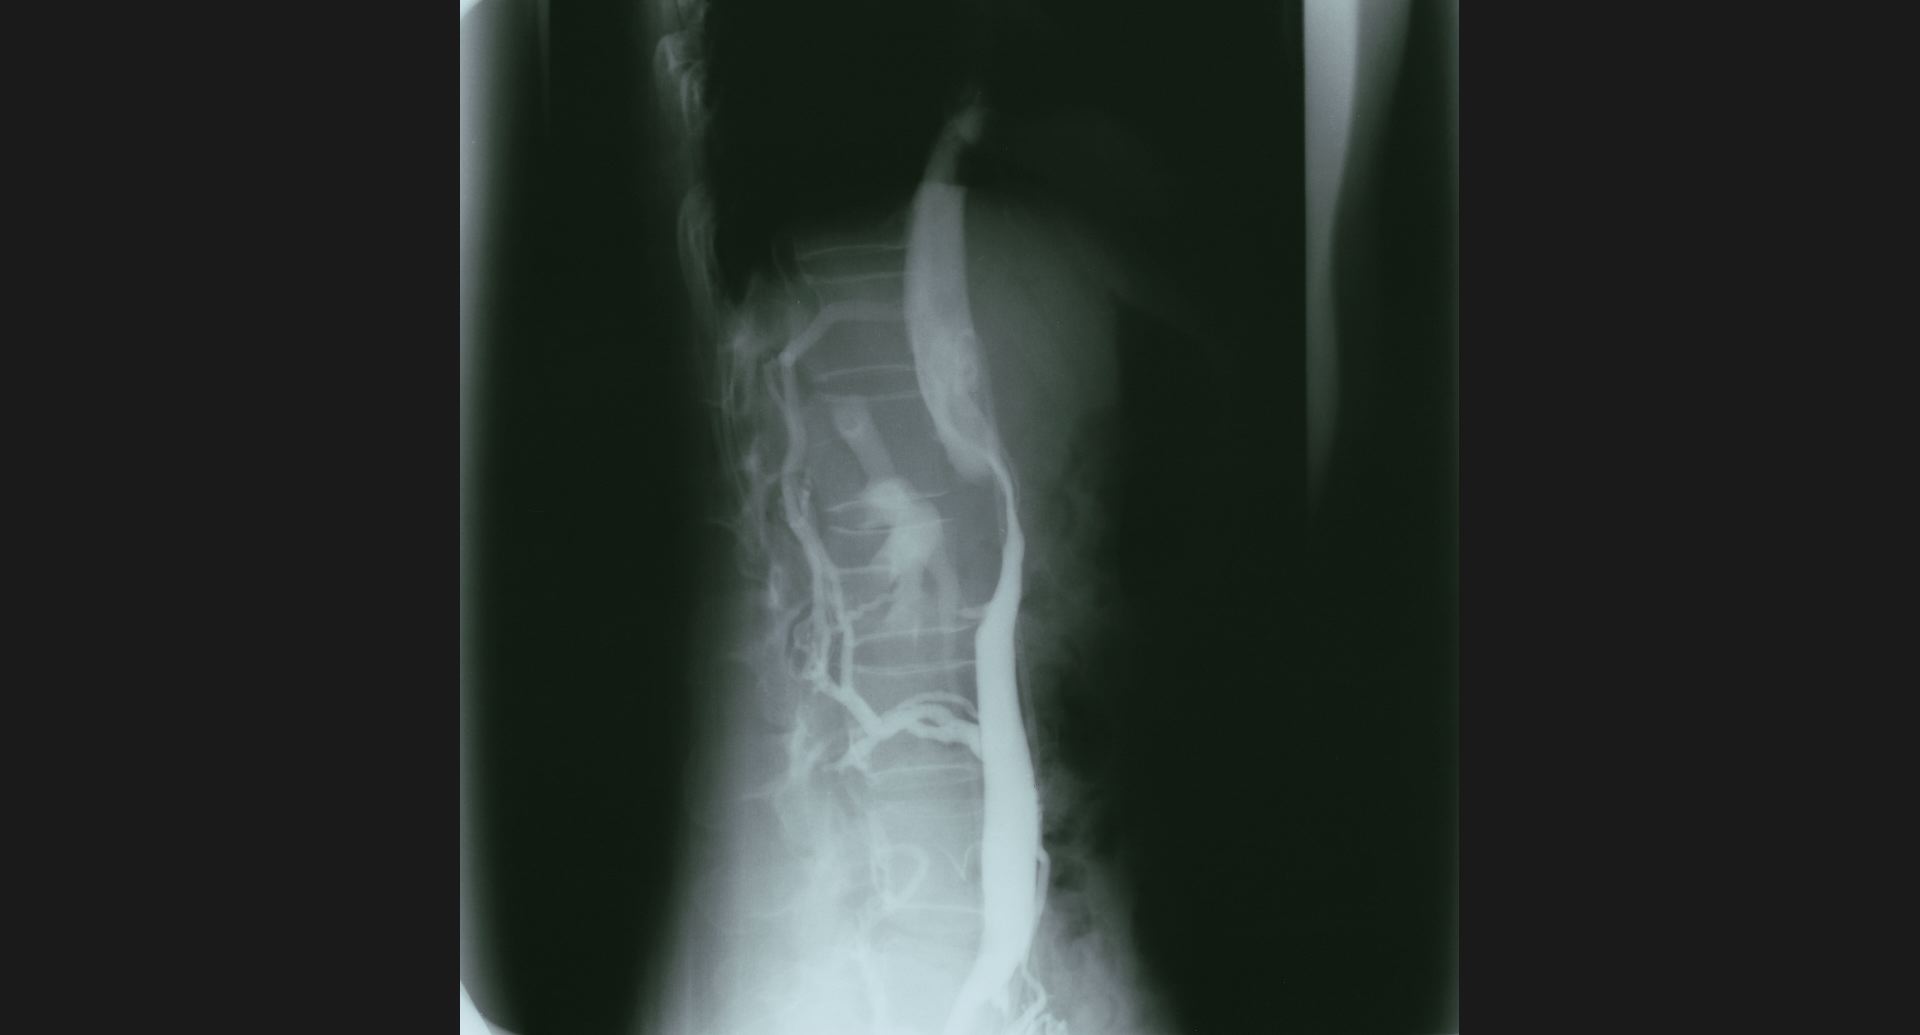

fig.11(59KB)

:IVC stenosis (cavography), lateral view

collateral vein。狭窄。